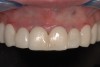

Fig 10. Final smile.

Figure 10

“Masking buildup” was performed (Figure 9), according to the concepts of immediate dentin sealing.14 A slightly opaque veneer composite cement was used for cementation and to enhance the masking effect (Figure 10).